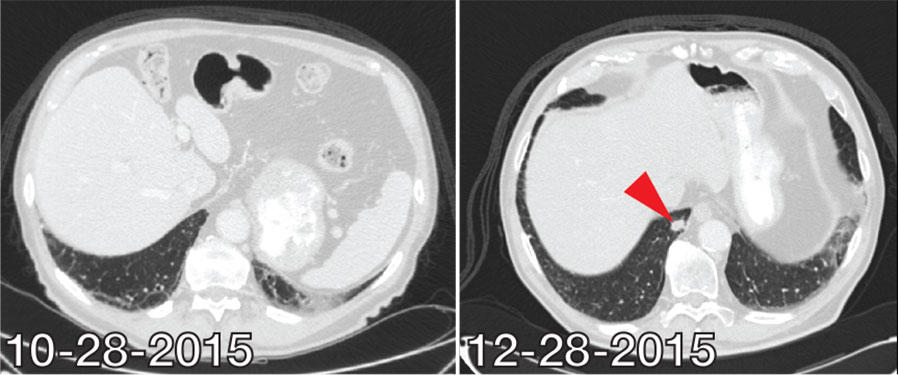

El momento de la aparición de efectos secundarios de la inmunoterapia es menos predecible que con cualquier otro tipo de tratamiento para el cáncer. Los pacientes que reciben inmunoterapia pueden presentar efectos secundarios poco después de recibir la primera dosis de un fármaco o mucho tiempo después de haber finalizado un ciclo de tratamiento.

Recientemente, doctores de MD Anderson informaron, por ejemplo, que un paciente en tratamiento por sarcoma presentó una complicación grave de diabetes alrededor de 3 semanas después de recibir una sola dosis del fármaco de inmunoterapia pembrolizumab (Keytruda).

La mujer de 47 años de edad, que no tenía antecedentes de diabetes y no había recibido inmunoterapia previamente, recibió el diagnóstico de cetoacidosis diabética en una consulta en la sala de urgencias de MD Anderson.

"Este caso de inicio abrupto en la edad adulta de diabetes mellitus tipo 1 es un ejemplo de un efecto secundario indeseado que puede surgir después de solo una breve exposición a un inhibidor de punto de control inmunitario", escribieron el doctor Patrick Chaftari y sus colegas en un informe del caso sobre esta paciente.

Los pacientes que reciben inhibidores de puntos de control deben ser "observados cuidadosamente" para poder diagnosticar en forma temprana y tratar complicaciones que pueden ser mortales, agregaron los autores.